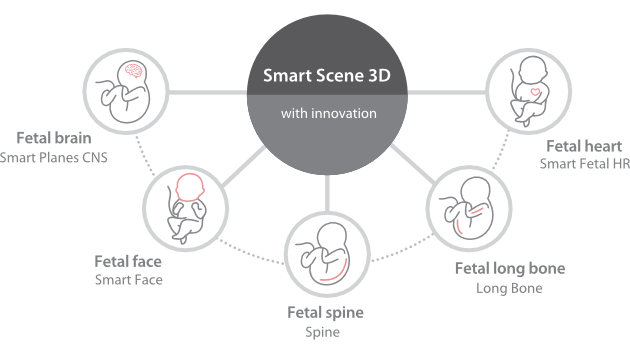

Consona presenta soluzioni nuove e concrete, che aiutano a effettuare diagnosi efficaci con semplicità, rivolgendosi a un'ampia platea di pazienti.

Indipendentemente dalle attività svolte in ospedale o in clinica, oppure se si desidera affinare le proprie capacità nella diagnostica per immagini generale negli ambiti della salute della donna o cardiovascolare, questa serie di soluzioni fornirà potenti strumenti per essere sempre un passo avanti.

Soluzioni di diagnostica per immagini complete con tecnologia ZST+

La piattaforma ZST+ è un'innovazione straordinaria, che rappresenta un'evoluzione nel campo dell'ecografia. Grazie alla trasformazione delle metriche a ultrasuoni dal beamforming convenzionale all'elaborazione basata sui dati di canale, supera la tradizionale limitazione del trade-off tra risoluzione spaziale, risoluzione temporale e uniformità dei tessuti, offrendo una qualità d'immagine eccezionale per infinite soluzioni di imaging con miglioramenti continui.